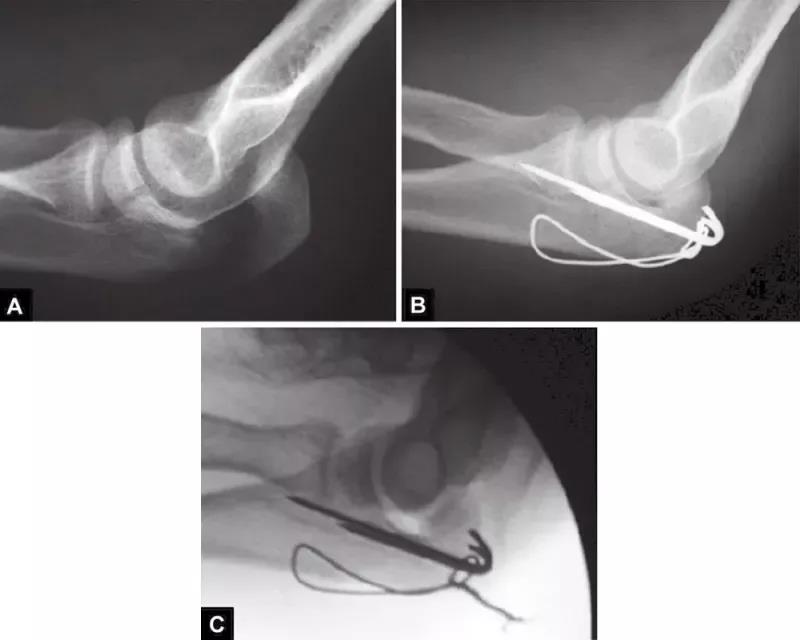

图3A~C关节压缩骨折在鹰嘴斜位片中完全隐匿。在箭头的部位变窄可能是一个提示。如果不知道这种可能性,医生就会忽略该手术X线片检查中明显的关节面压缩骨折。术后标准的侧位片良好地显示了关节面压缩骨折。该医生未能完成最初的手术目标